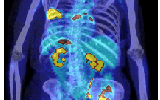

分子影像学:一场悄然发生的医疗革命

分子影像学源于细胞生物学、分子生物学和影像技术学的结合,所涉及的领域大大超越传统临床知识结构下的影像学,是对癌症早期诊断和分期治疗最有价值的技术研究,它既能有效推进靶向性治疗也能够节省癌症医疗费用的浪费,更将对上游制药企业的新药研发带来革命性改变。

分子影像

癌症

新药研发